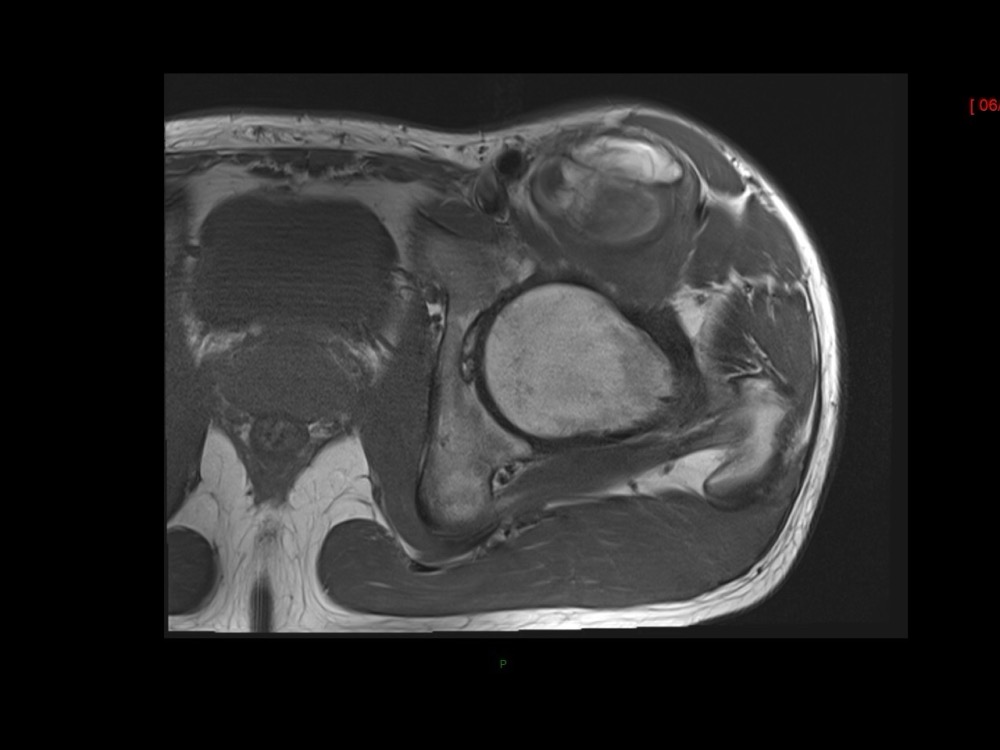

Moalla / Mihoubi-Bouvier / Drapé 18/05/2022